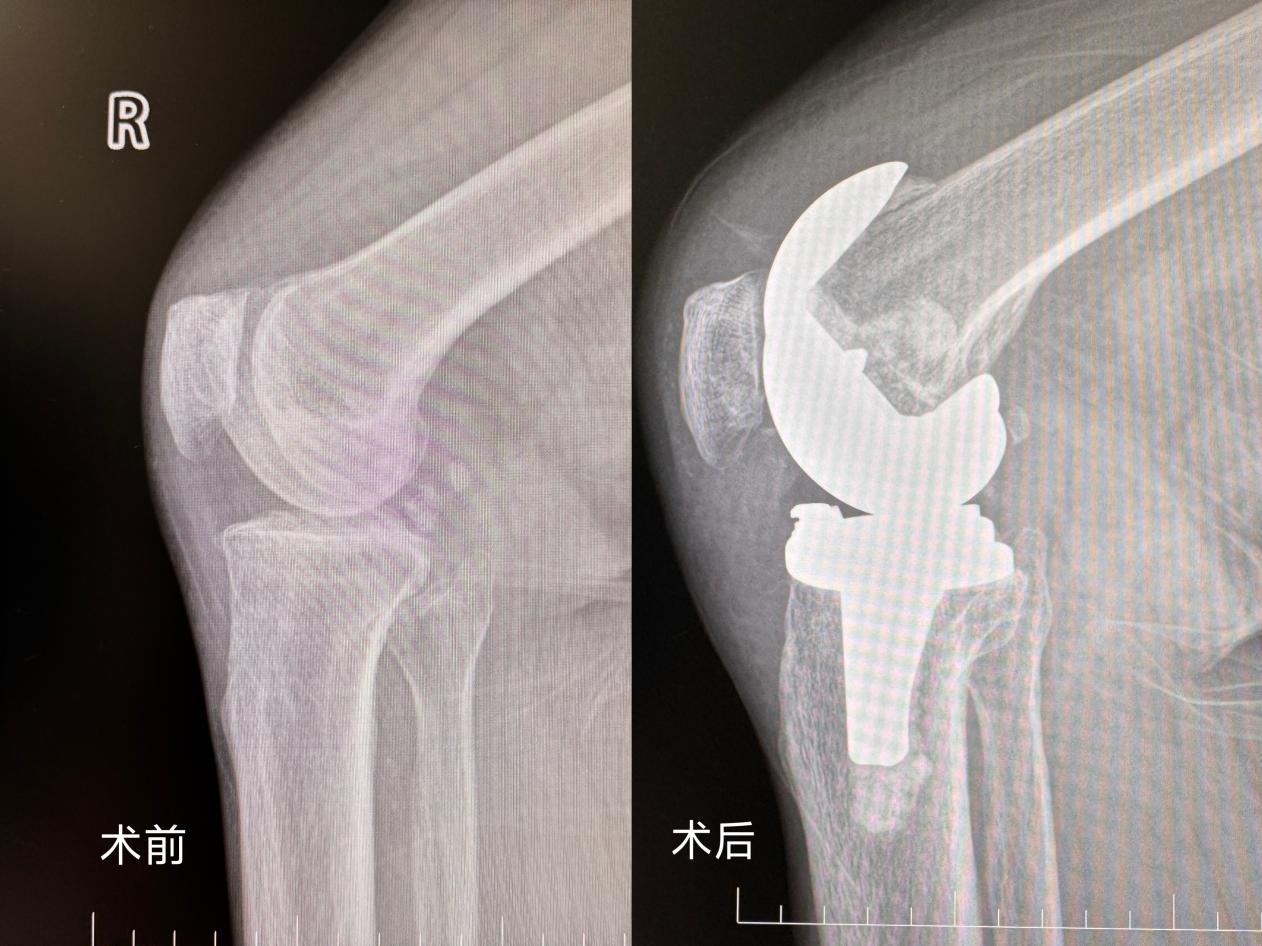

入院后,医生为张伯伯安排了 CT、核磁等一系列检查。检查结果显示:右膝关节退行性变严重,软骨磨损殆尽,软骨下骨质也出现了损伤,半月板、韧带、肌腱多处受损,关节腔内还有积液,周围软组织也受累肿胀。鉴于保守治疗已无效果,张伯伯最终决定接受手术治疗。

手术由湖南妇女儿童医院骨科副主任康长周主刀,在骨科、麻醉手术部、放射科等多学科的紧密协作下,膝关节置换术顺利开展。手术过程中,医生精准地取出了严重变形的膝关节,换上了适合的人工关节,仔细检查关节活动度后,进行了细致的缝合。整个手术过程十分顺利,出血量控制在合理范围内,全程仅用时 2 小时。